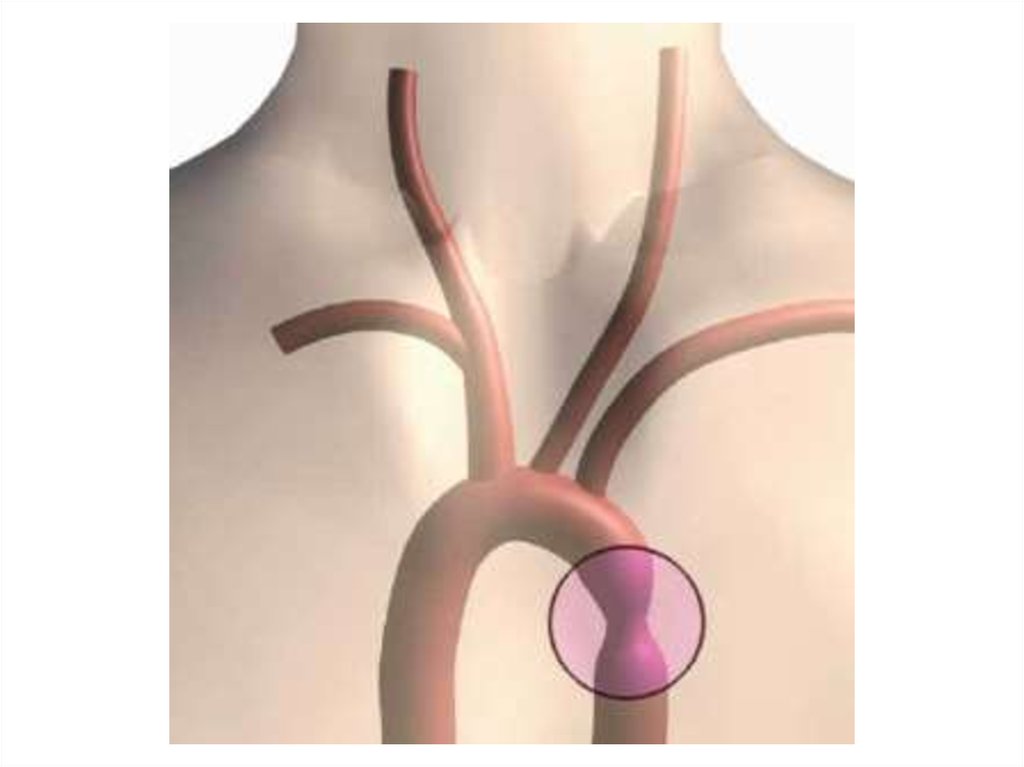

Нормальный диаметр корня аорты: медицинские нормы и отклонения